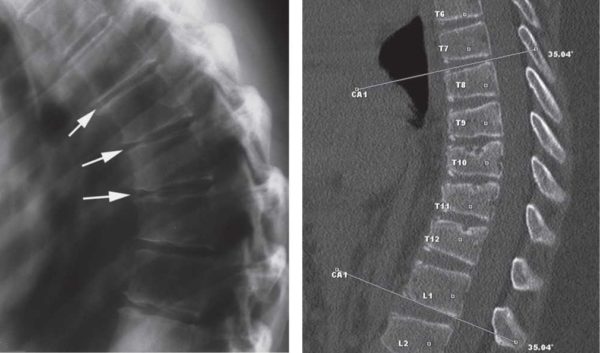

На рентгеновских снимках отчетливо просматривается клиновидная форма позвонков и степень искривления

При юношеском кифозе позвонки постепенно деформируются и приобретают форму клина. На рентгеновских снимках, сделанных в боковой проекции, они выглядят почти как треугольники. Кроме этого, сокращаются мышцы груди и передней брюшной стенки, что приводит к развитию контрактуры – стягиванию и сужению мышечного корсета.

Для диагностирования степени изгиба грудного кифоза применяют метод Кобба, когда по рентгеновскому снимку в боковой проекции к замкнутым пластинам позвонков проводят касательные линии и выстраивают внутренние перпендикуляры. Угол искривления, образованный линиями при кифозе 3 степени, составляет более 50 градусов.